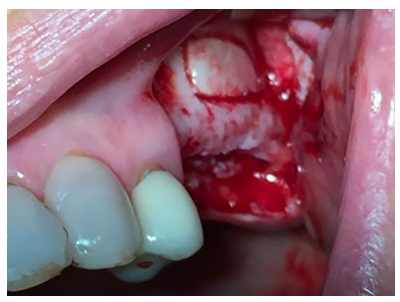

El abordaje quirúrgico fue realizado mediante una incisión lineal crestal y dos descargas verticales, mesial y distal, procediendo al despegamiento mucoperióstico para la obtención de un campo quirúrgico adecuado. Se realizó el diseño de una ventana lateral con piezoeléctrico (VarioSurgery®) (Figura 4), despegándose a continuación la membrana sinusal sin perforación alguna (Figura 5). A continuación, se procedió al relleno mediante un compuesto de fosfato de calcio-potasio-sodio bioactivo (Osseolive®) (Figura 6), acompañado de la colocación de una membrana de ácido poliláctico (EPI-Guide®) (Figuras 7 y 8), finalizando la intervención con la reposición del colgajo mucoperióstico y sutura con poliamida de 4/0 (Supramid®) (Figura 9).

Se realizó una incisión lineal crestal con descarga distal para la obtención del campo quirúrgico. Se utilizó la técnica de fresado biológico a 100 rpm insertándose 3 implantes en posición 25, 26, 27 de 3,5 mm x 10mm (SIN Unitite®), con un torque de 50 N/cm obteniéndose una correcta estabilidad primaria (Figura 11). Tras la colocación de los tornillos de cierre, se procedió a la sutura del colgajo con Supramid® 4/0 aguja 3/8 (Figura 12).